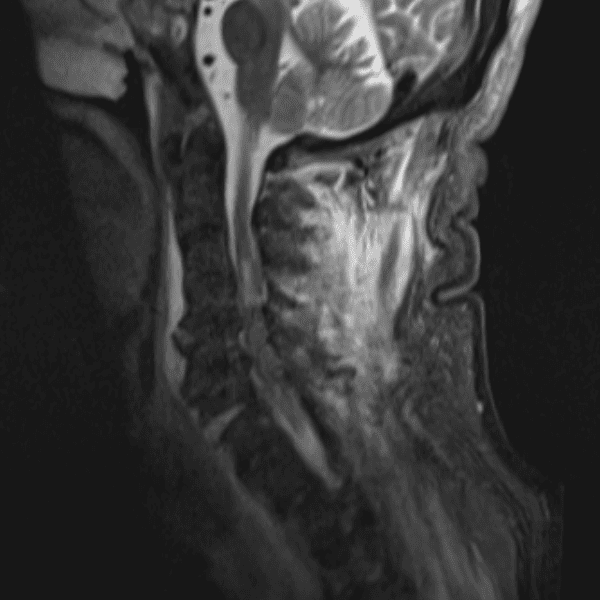

Simulates call by including subtle or difficult cases and some normals.

35 cases